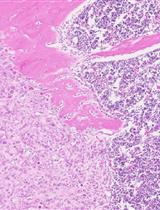

The host microenvironment plays a prominent role in tumor growth, angiogenesis, invasion, metastasis, and response to therapy. Orthotopic tumor model mimics the natural environment of tumor development and provides an effective approach to investigate tumor pathophysiology and develop therapeutic strategies. This protocol describes the technique involving injection of colorectal cancer cell suspension into the intestinal wall of mice to establish an orthotopic colorectal tumor model.

Various murine models have been developed to facilitate studies of human cancers and allow better understanding of mechanisms contributing to tumor growth. While heterotopic xenograft models involve implanting cancer cells into the flank of immunocompromised mouse subcutaneously, orthotopic tumor models more closely resemble the original tumor development due to the implantation of tumor cells directly into the organ of origin (Richmond and Su, 2008). Although orthotopic xenograft models are technically challenging and labor-intensive, orthotopic transplants are able to more accurately mimic human tumor and better predict a patient’s response to chemotherapy in comparison with heterotopic transplants because of the effects of tumor microenvironment (Talmadge et al., 2007). With increased knowledge regarding the important role of tumor-host cell interaction during tumor progression, genetically engineered mouse (GEM) models using immunocompetent mice extend our ability to model the complexity of human cancers (Gopinathan and Tuveson, 2008; Zitvogel et al., 2016). However, GEM models are more expensive, often require months to a year to develop tumors, and have the drawbacks regarding the heterogeneity of tumor frequency, latency and growth. By contrast, xenografts are less expensive, require less time to establish tumors, and have better reproducibility (Vandamme, 2014). In this protocol, we describe the procedure of generating orthotopic colorectal cancer by injecting human cancer cells into immunocompromised mice (Tseng et al., 2007; Liao et al., 2015).